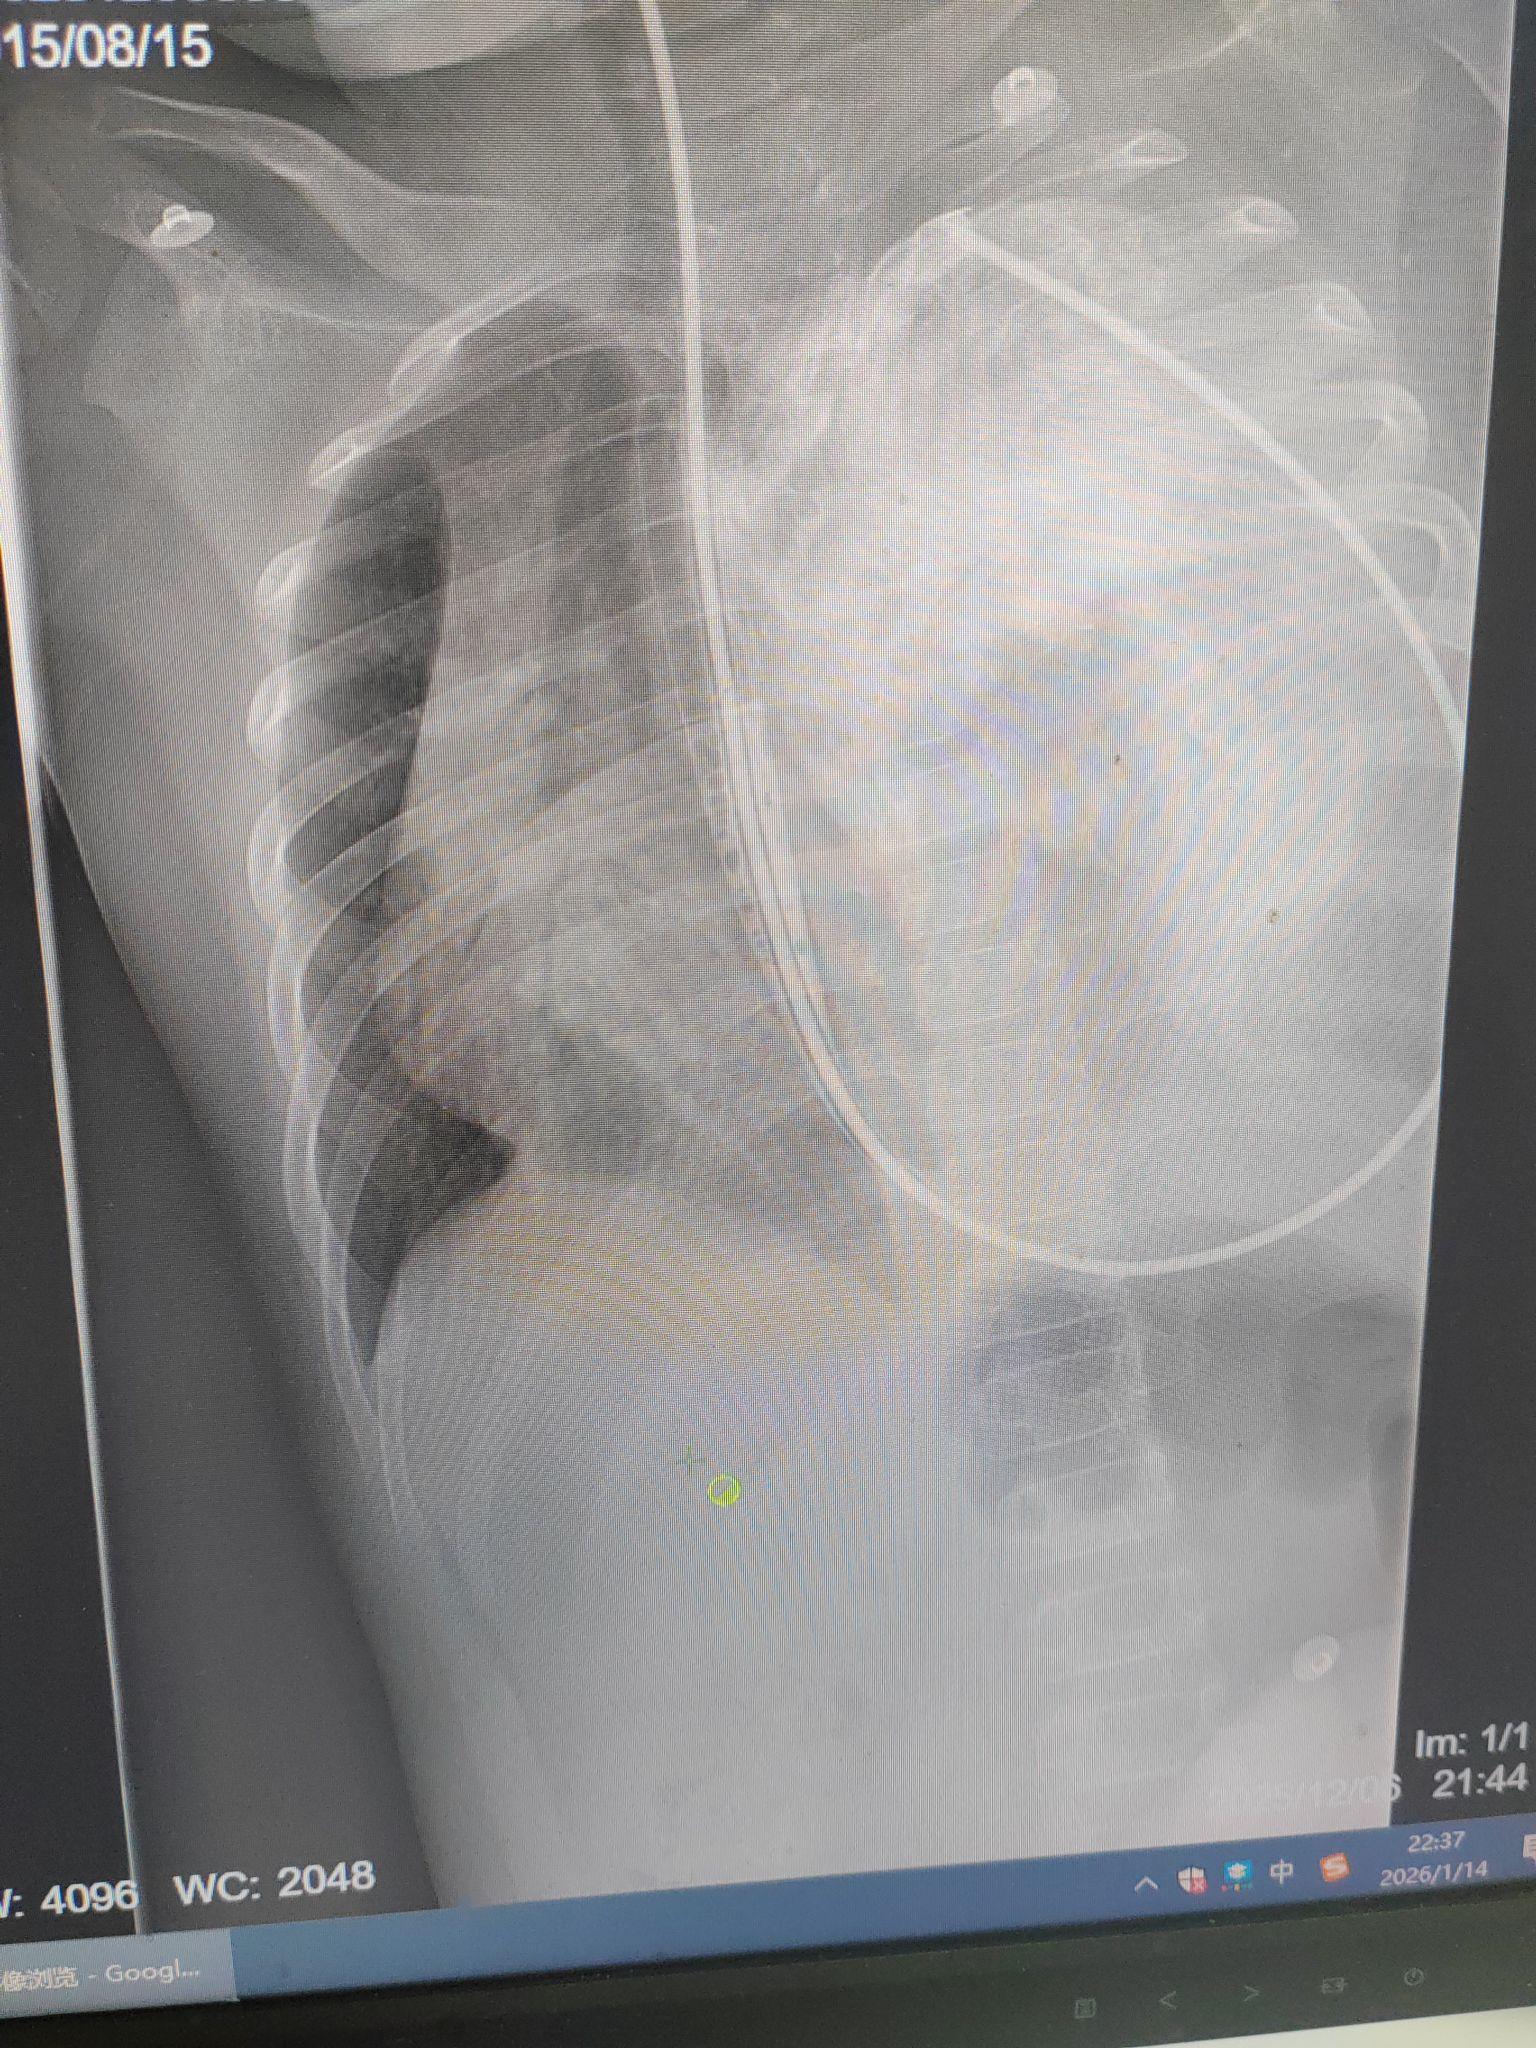

【临床诊断】膈疝

血常规+超敏C反应蛋白(急诊):WBC 25.54X10⁹/LNEUT# 20.35X10⁹/L LYMPH# 2.38X10⁹/L NEUT% 82.9% LYMPH% 9.7% CRP2.13mg/L,免疫四项,凝血四项均未见明显异常,胸部DR提示:左侧胸腔大量积液,建议CT扫描进一步检查。

3,辅助检查:血常规+超敏C反应蛋白,胸部DR结果,以及进一步胸部CT扫描结果:食管裂孔疝,胃体及部分肠管疝于左侧胸腔。左肺不张,右侧胸腔积液。

患儿入院后给予给予清洁肠,给予补液,查胸部CT+上,下腹部CT平扫后考虑食管裂孔疝:胃体及部分肠管疝于左侧胸腔;左侧肺不张,右肺少量炎症:右侧胸腔积液,考虑食管裂孔疝,请普通外科会诊后诊断为膈疝-左侧胸腔胃?后请胸外科会诊:患儿胃肠脏器进入左侧胸腔,考虑单纯洗胃,胃肠减压效果不佳,有胃坏死风险,建议转胸外科尽快手术治疗。

2025-12-07上消化道造影食管:走行正常,管壁柔软,光滑,粘膜规则,蠕动如常,未见狭窄。胃呈虾状位于膈上,胃容积较昨日明显缩小。十二指肠未显影。食管裂孔疝全胃疝于膈上2025-12-07CT平扫胃营养管置入术后,此次扫描示:胃内见引流管影。胸廓对称,肋骨,胸椎及其他所见骨质未见明显破坏,胸壁软组织未见异常;左肺体积明显减小,见片状高密度影及充气支气管征;右肺见条索状高密度影;纵隔稍右移,心影及大血管形态,大小未见明显异常,纵隔内未见肿块及肿大淋巴结;右侧胸腔见液体密度影。1。与2025-12-06日胸部CT对比:2。胃胃营养管置入术后;胃体及部分肠管疝于左侧胸腔,考虑膈疝3。左肺受压减轻,较前复张,双肺炎症伴少量实变4。右侧胸腔积液较前略增多。